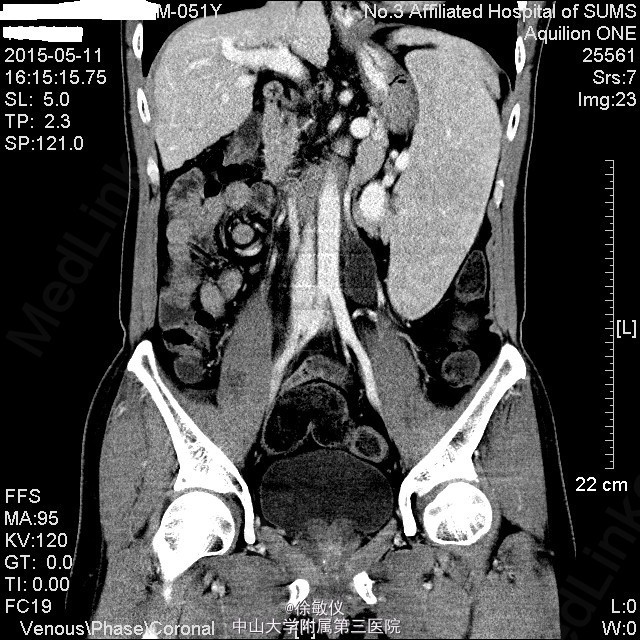

查体:生命体征平稳。皮肤无黄染,巩膜轻度黄染,未见肝掌、蜘蛛痣,未见瘀点或瘀斑。心肺查体无特殊。腹部外形平坦,未见腹壁静脉曲张,腹软,无压痛、反跳痛,肝肋下未触及,Murphy(-)。脾肋下6cm,质软,边界光滑,无压痛。 辅查:血常规:WBC 2.03x10E9/L,Hb 106g/L,PLT 51x10E9/L。 生化:白蛋白34.6g/L,转氨酶正常。 凝血:凝血酶原时间17.2sec,凝血酶原活动度61%。 全腹螺旋CT平扫+增强:1、肝硬化,门脉高压,脾大,食道下段胃底静脉曲张,附脐静脉开放,脾静脉增粗、迂曲。2、慢性胆囊炎。3、前列腺增生。4、全腹CTA:右侧副肾动脉形成。5、左肺下叶少许慢性炎症。